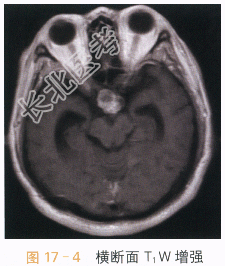

读片分析:头颅CT平扫见鞍上异常软组织影,并可见多发钙化,局部见“蛋壳样钙化”,横断面T₁W见鞍上异常软组织信号灶,呈等高信号影,T₂WI见病灶表现为囊实性肿块;增强扫描实性部分可见明显强化,囊性部分未见明显强化,但正常垂体结构能显示。结合患者临床,可考虑颅咽管瘤。